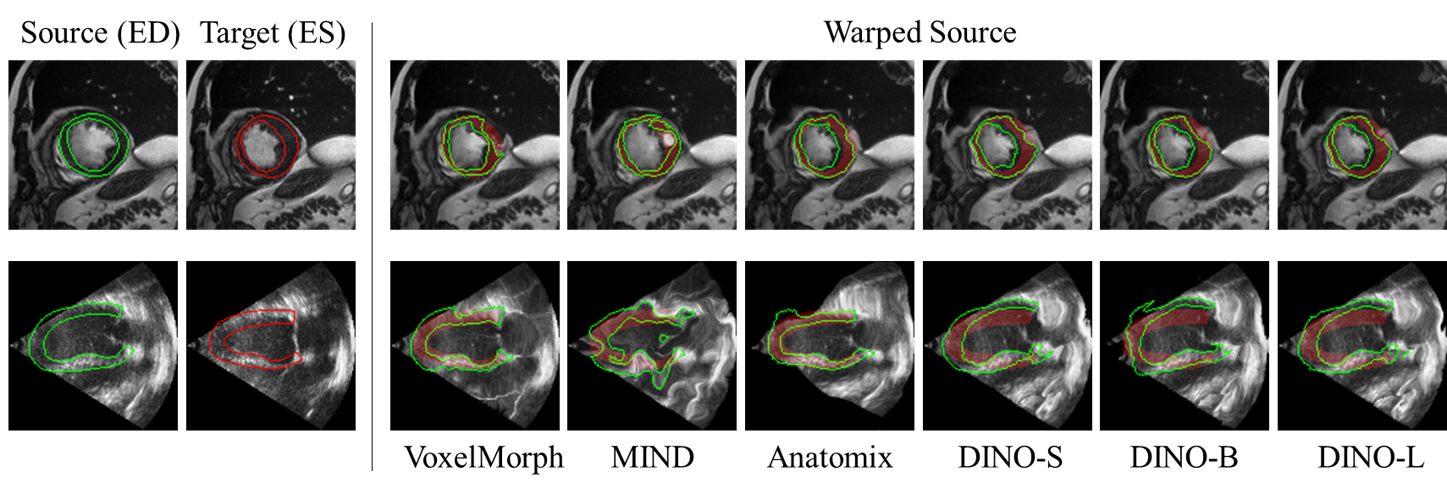

3D Registration of Cardiac MRI Volumes: For 3D image registration on the ACDC dataset [38], DINOv3 establishes a strong baseline, moderately outperforming other methods. Table 16 presents the results for cardiac MRI volume registration. Quantitatively, feature-based registration methods are on par with the widely used VoxelMorph method. However, qualitative differences are evident in the warped segmentation maps. As illustrated in the first row of Figure 8, DINOv3 demonstrates superior correspondence, particularly in scenarios involving occlusions. In instances where tissues inside the myocardial segmentation ring exhibit intensity differences, DINOv3 features yield the smoothest and most well-aligned results.

Figure 8: Qualitative results of cardiac image registration on the ACDC (top row) and CAMUS (second row) datasets. The first two columns show source and target images with ground truth myocardium segmentation contours. The subsequent columns display warped source images produced by different registration methods. Each warped image is overlaid with warped myocardium contours, with red highlighting the ground truth End-Systole (ES) myocardium.